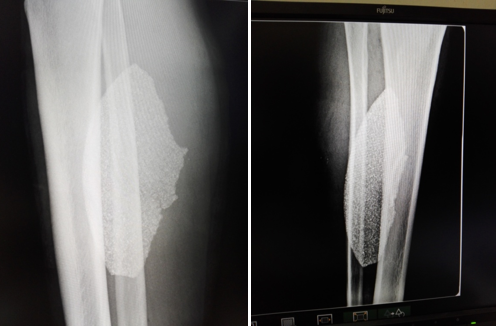

Radiographic studies (Figure 1) showed the presence of a large shear disc fragment in the soft tissues of the leg and hematological studies showed leukocytosis with a predominance of segmented.

Figure 1 Radiographic images extend the antimicrobial spectrum and perform polyvalent antitetanus and antigangrenous prophylaxis.